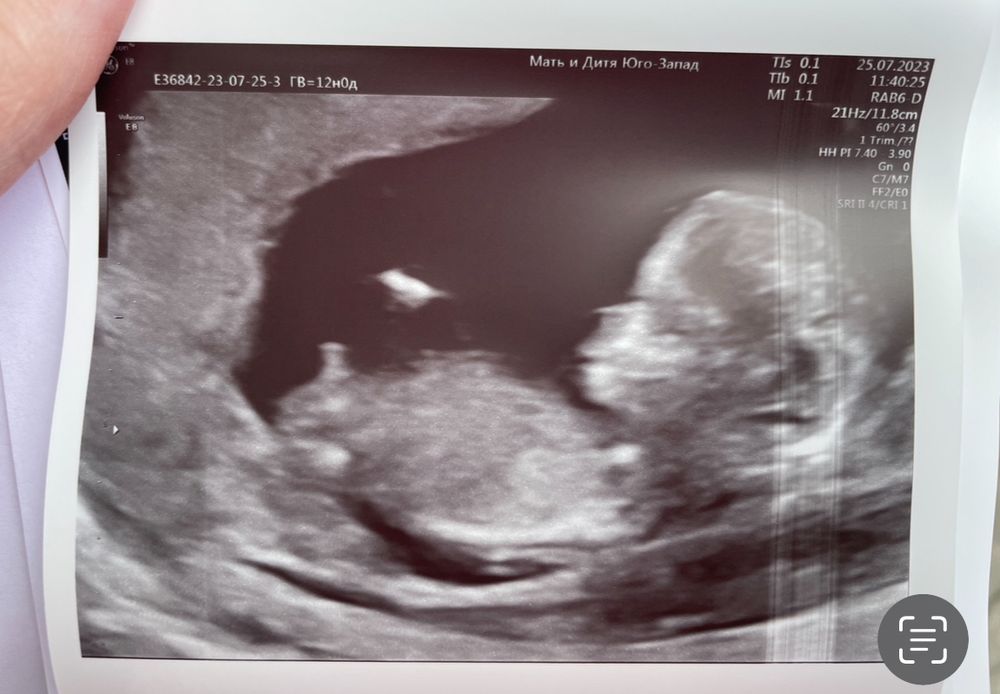

Была на 1 скрининге. На опрос, какой пол, врач сказал что слишком маленький срок, пол будет виден только после 16 недели, но👆 по *какому то прикреплению похоже что мальчик. И опять оговорился, что точно только после 16 недели

А что мы можем думать😂вообще на таком сроке смотрят по половому бугорку, это такая палочка как бы идущая ниже животика если она прямо идет как бы параллельно позвоночнику то девочка если вздернута вверх то мальчик